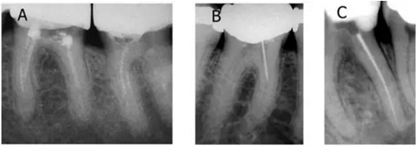

不同類型的分離器械;A. 螺旋輸送器;B. GG鉆;C. 整支鎳鈦銼 (由Dr. Peter Spili提供)

分離在根管內(nèi)的器械不僅限于根備銼,還包括GG鉆、側(cè)壓針、螺旋輸送器、沖洗針頭和超聲蕩洗針等,一般原材料多為鎳鈦、不銹鋼和碳鋼。